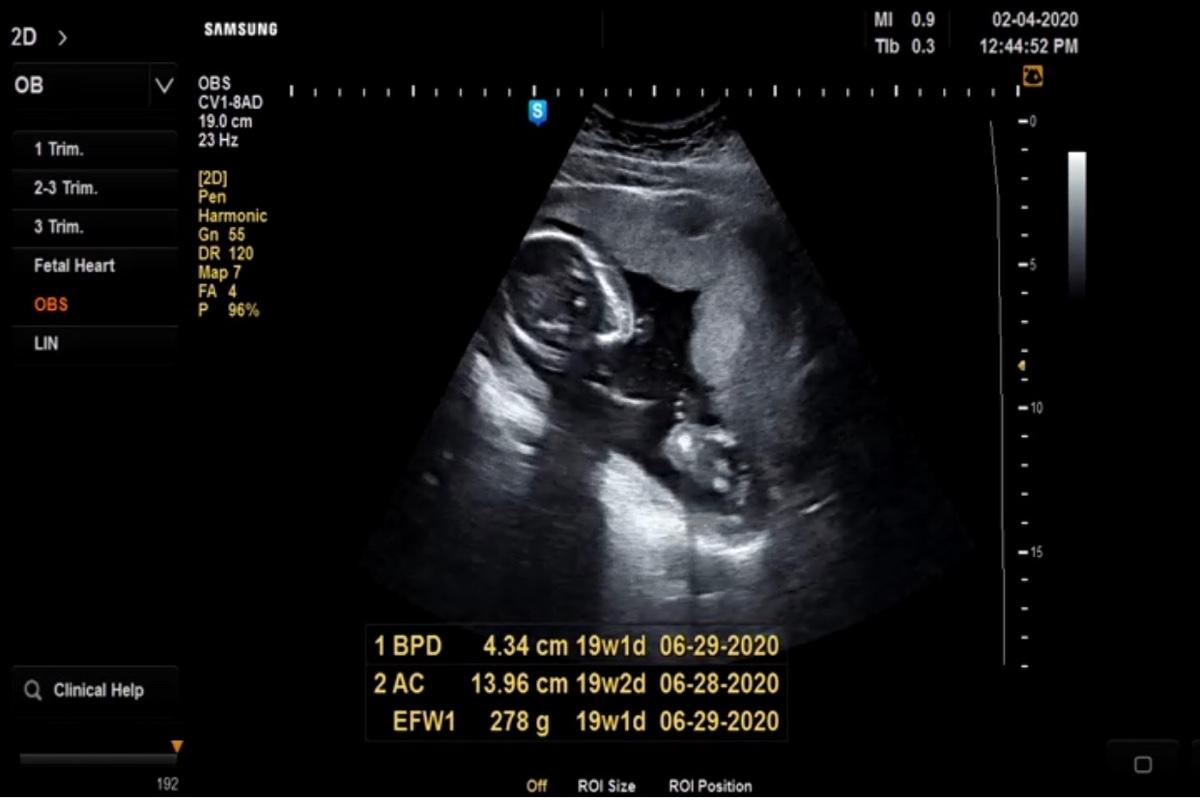

2020/02/04。臨時決定去產檢!

2月份的產檢日其實是2/22才對~

只是在2/1那天,我去做了羊膜穿刺後~

有點點出血,有點擔心,因此2/4我自己跑去給醫生看診~

還好⋯醫生照了超音波、也內診過了!

確定寶貝沒問題了!我才放心~